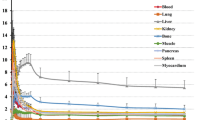

Figure 4 shows the decay-corrected time-activity curve of the %ID for typical source organs (brain, liver, spleen, lung, kidney, heart content, heart wall, muscle, red marrow, small intestine contents, gallbladder, upper large intestine contents and urinary bladder) from the six volunteers and the mice experiments. A significant difference between the %ID from humans and mice was observed in the brain, liver, spleen, heart contents, red marrow and urinary bladder, and these differences propagated the different results regarding dose estimation. In human subjects, 18F uptake in the gallbladder contents and the intestines (Figure 4J,K,L) indicated larger individual variations in radioactivity uptake relative to other organs (e.g. the kidney as shown in Figure 4E). Radioactivity uptake in the upper large intestine showed propagation of both ligand kinetics and inter-subject variation from the gallbladder (Figure 4K,L). Scheinin et al. previously reported that inter-subject variation in ligand uptake ([11C]PIB) in the gallbladder may be due to the quality and quantity of post-injection food intake [7]. In the present study, the subjects drank water during the interval between the first and second PET scans. This may have been responsible for the increase in inter-subject variation regarding the gallbladder. Furthermore, because the gallbladder uptake in some subjects had declined or remained at a low level at the final time points, we assumed that there was only physical radioactive decay after the last PET scans. However, this assumption may have led to a conservative estimation of the absorbed dose.

Decay-corrected time-activity curves of %ID. (A) Brain, (B) liver, (C) spleen, (D) lung, (E) kidney, (F) heart content, (G) heart wall, (H) muscle, (I) red marrow, (J) SI contents, (K) gallbladder, (L) ULI content and (M) urinary bladder for individual human (dashed black line) and averaged mice extrapolation (n = 4 at each time point, grey line). The solid black line indicates fitted curve using exponential function from all subjects' data points. The urinary bladder curve indicates accumulated activity excreted at all voiding/sampling moments.